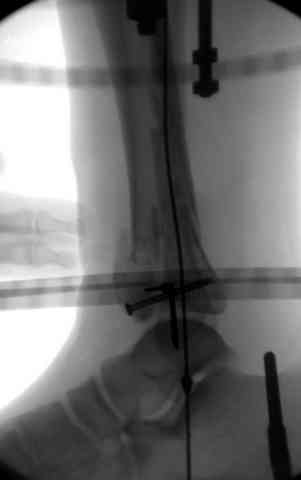

Дистрагированные лигаментотаксисом костные фрагменты иногда организуются в нужном направлении и во время операции облегчается репозиция отломков.

Дополнительные ренгенограммы после дистракции и

обязательная комьютерная томография дают возможности разузнать топографию расположения фрагментов, что немаловажно для планирования хирургического доступа.

Здесь выставлена пара случаев перелома пилона, оба

случая леченные этапным наружным фиксатором.

Второй случай фиксирован аппаратом Илизарова.